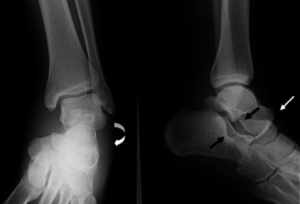

- Конечность приобретает неестественное положение, сустав часто выступает немного вперед. На снимке можно отчетливо увидеть трещину.